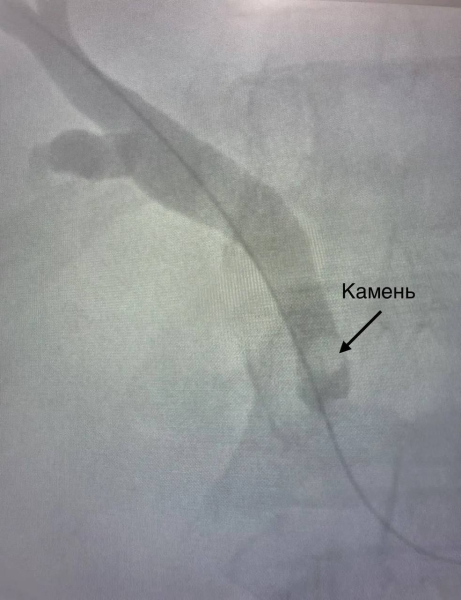

Под контролем рентгена доктора провели мини-инвазивную операцию. Через небольшой разрез пациенту ввели проводник, через который доктора при помощи инструментов выполнили удаление камня.

«Через протоки печени мы ввели особый инструмент в виде петли, захватили камень и достали его, задействуя твердый тубус. Действовать необходимо было аккуратненько, просчитывая каждый мм, в данном и была трудность. Схожую операцию мы проводили в первый раз, все прошло удачно. Пациент всегда был в сознании, под местной анестезией» — гласит рентгенхирург Зоя Антропова.